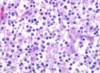

What type of cells are seen and what are their function?

Gitter cells (foamy cytoplasm)

Function: microglia that ingest myelin debris